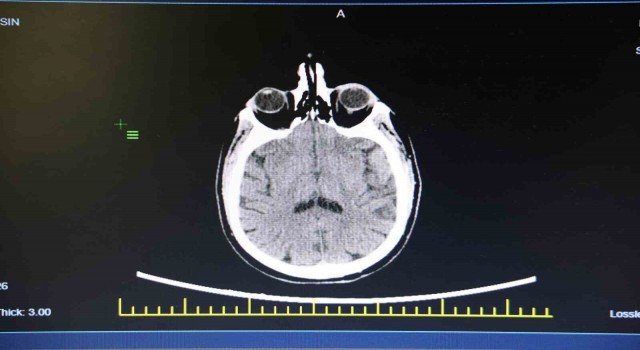

Elazığ Fethi Sekin Şehir Hastanesinde görevli Kulak Burun Boğaz (KBB) Uzmanı Prof. Dr. Öner Sakallıoğlu, işitme kaybı hakkında açıklamalarda bulunarak vatandaşlara tavsiyelerde bulundu. İşitme kaybının toplumdaki her yaşta görülebileceğini ve sıklıkla rastlanabileceğini aktaran Prof. Dr. Öner Sakallıoğlu, "İşitme kaybı her yaşta görülebildiği için bulunduğu dönem itibariyle gerek bir engel teşkil etmesi gerekse de iletişimi engellemesi ya da çocuklarda dil gelişmesi sorunlarına yol açması bakımından oldukça önem taşımaktadır. İşitme kaybı genelde hastaların işitmelerinin az olmasını ifade etmesiyle ortaya çıkar. Yeni doğan bebeklerde pek mümkün olmasa da onlarda yapılan çeşitli testlerde bu işitme kaybı ortaya çıkartılabilmektedir. Tedavi süreçleri genel olarak yaşla ilgili sebeplere bağlı olarak değişebilmektedir. Çünkü oldukça farklı sebepleri olabilir. Özellikle çocukluk çağı başta olmak üzere erişkin çağ ve daha ileri yaş olan yaşlılık döneminde çeşitli yöntemlerle tanı ve tedavisi yapılabilmektedir. Halk arasında doğru olarak bilinen fakat tıp dilinde yanlış olanların belki de en önemlisi işitme kaybının tedavisinin olmayacağı yönünde bir görüş hakim. Fakat işitme kaybının çok büyük bir kısmı tedavi edilebilmektedir. Gerek ameliyat yöntemleriyle gerekse de tedavi yöntemleriyle işitme kayıplarının çok büyük bir kısmı tedavi edilebilmektedir. Özellikle kulak çöplerinin kullanımı çok doğru olmayabilir. Toplumda çoğu insan kulağını temizlemek amacıyla kulak çöpü ya da başka cisimler kullanmaktadır. Bunların sıkıntılara yol açma ihtimalleri oldukça yüksektir. Kulak salgısının azaltılmasına yol açarak kulağın kurumasına ve kaşıntıya yol açabilir. Onun haricinde kulakta yabancı cisimler oluşturabilir. Bunlar kulak zarı yırtılmasından tutalım da kulak kanalının çizilmesi ve dış kulak enfeksiyonlarının ortaya çıkması gibi sorunlara neden olabilir. Bunların tedavisi mümkün fakat kulak çöpü gibi yabancı cisimlerin kullanılmasını çok tavsiye etmemekteyim. Çoğu vatandaşta dış kulak kanalından sarımsı bir şekilde gelen sıvı akıntısı olmaktadır. Bunlar kulağımızın normal bir salgısıdır. Bunların illa temizlenmesi gerekmiyor. Daha önce bahsettiğimiz gibi bunların fazlaca temizlenmesi dış kulak kanalında travmalara belki de istemediğimiz enfeksiyonlara yol açabilmektedir. Bu yüzden sakıncası bulunmaktadır" dedi.